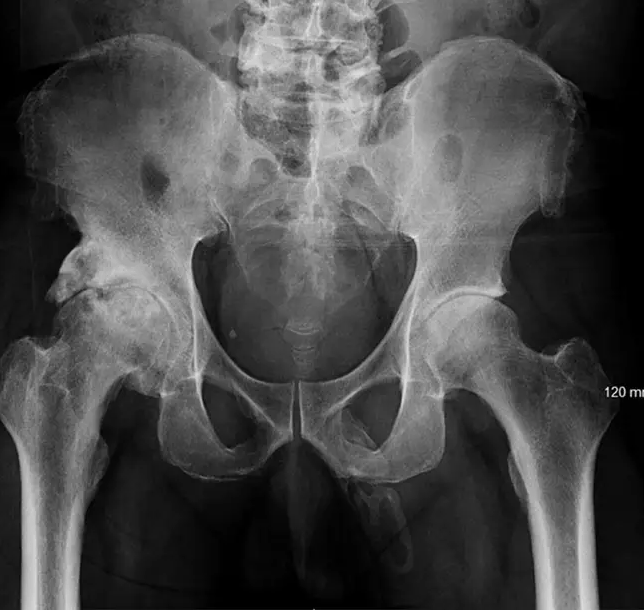

Lekári vykonali rozsiahlejšie röntgenové vyšetrenie, aby si boli istí, či si tento pacient nezlomil aj nejaké iné kosti. No po výslednej snímke zostali v šoku. Zistili totiž, že v jeho penise sa tvoria kostné bunky. Lekári mužovi svoj nález oznámili, no ten ich ignoroval a okamžite opustil nemocnicu. Možné je, že sa zľakol a odišiel. Röntgenové vyšetrenie panvy vykonané na vylúčenie akejkoľvek zlomeniny ukázalo závažné asymetrické degeneratívne zmeny pravého bedra. Bola evidentná rozsiahla kalcifikácia pozdĺž penisu. Zatiaľ čo prípady osifikácie penisu sú skutočne veľmi zriedkavé, v lekárskych záznamoch bolo hlásených necelých 40 takýchto prípadov.